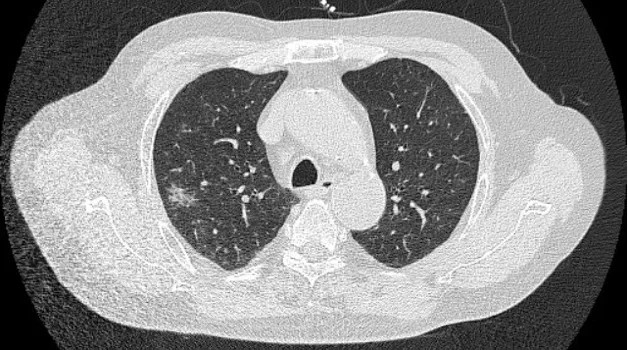

2025年5月27日肺部CT平掃影像

第三階段(2024年7月-2025年5月):轉(zhuǎn)診??漆t(yī)院康復(fù)治療后仍遺留舌體偏斜、飲水嗆咳,多次肺部CT顯示游走性炎癥病灶,肺功能顯著受損(DLCO 50-60%),激素減量困難,血壓血糖控制不佳,治療陷入僵局。